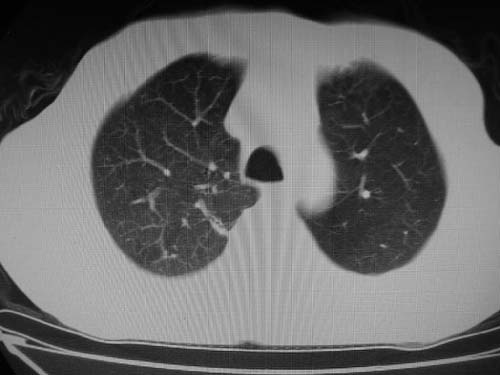

男,80岁

双肺陈旧性病变,左肺动脉高压.

)考虑肺动脉扩张,右心室增大,主动脉弓段正常位弓后段明显变小(不会是动脉导客未闭吧,不知患者有何症状病史)0。2)右肺上叶继发性肺结核。3)右侧胸膜增厚、钙化,左侧胸膜反应。

右肺上叶尖段结核;左肺下叶占位?建议增强扫描。右侧胸膜增厚;右肺局限性肺气肿。

结合患者年龄,不除外左下肺扩张性动脉瘤,建议胸透是否有扩张性博动,以便确诊。

肺动脉高压,左肺动脉瘤样扩张。

肺a高压